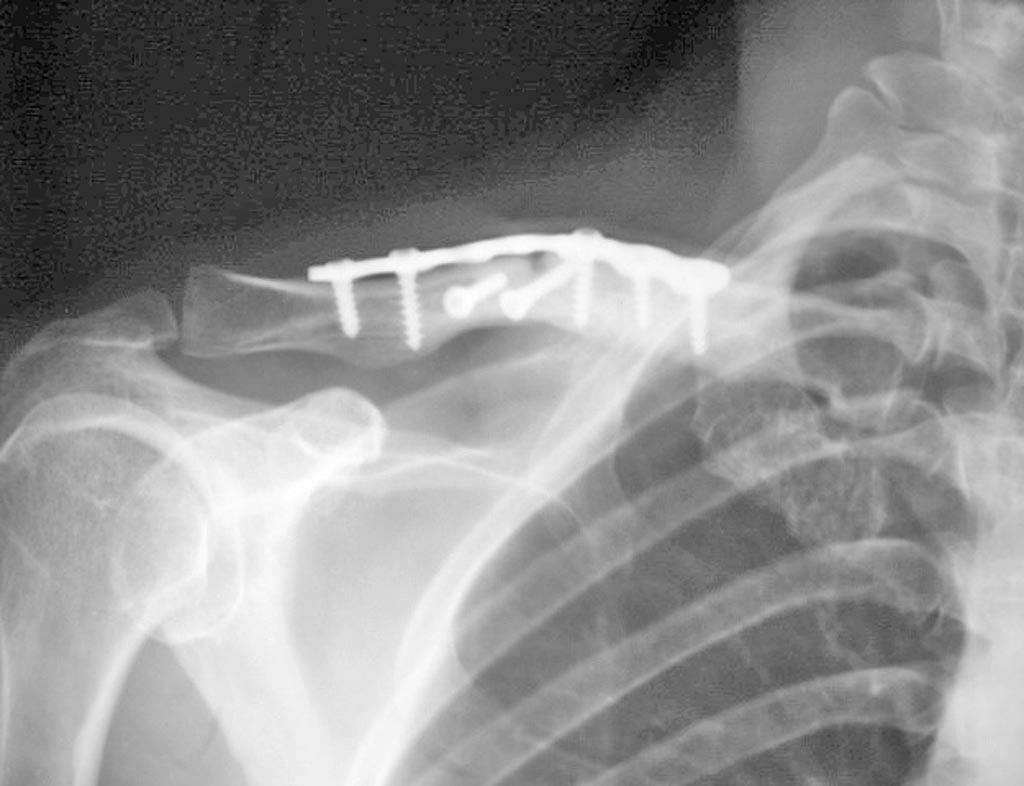

男,36,右锁骨骨折内固定一年,请问,愈合好吗,怎样描述

对位对线可。骨折线可见。

对位对线可,一年了骨折线仍看见,应该说愈合的不好,不在钢板上的这两个钉子不知有什么用?

对位对线可,骨折线可见,折端边缘骨质硬化。

对位对线可。愈合欠佳。不在钢板上的两个钉子不清楚原因

我想是固定骨片所用。本例为延迟愈合。

髓腔中下部骨质致密,下缘皮质完整,应该说---愈合尚可,纵行透亮区---不排除螺钉所致---需结合临床。